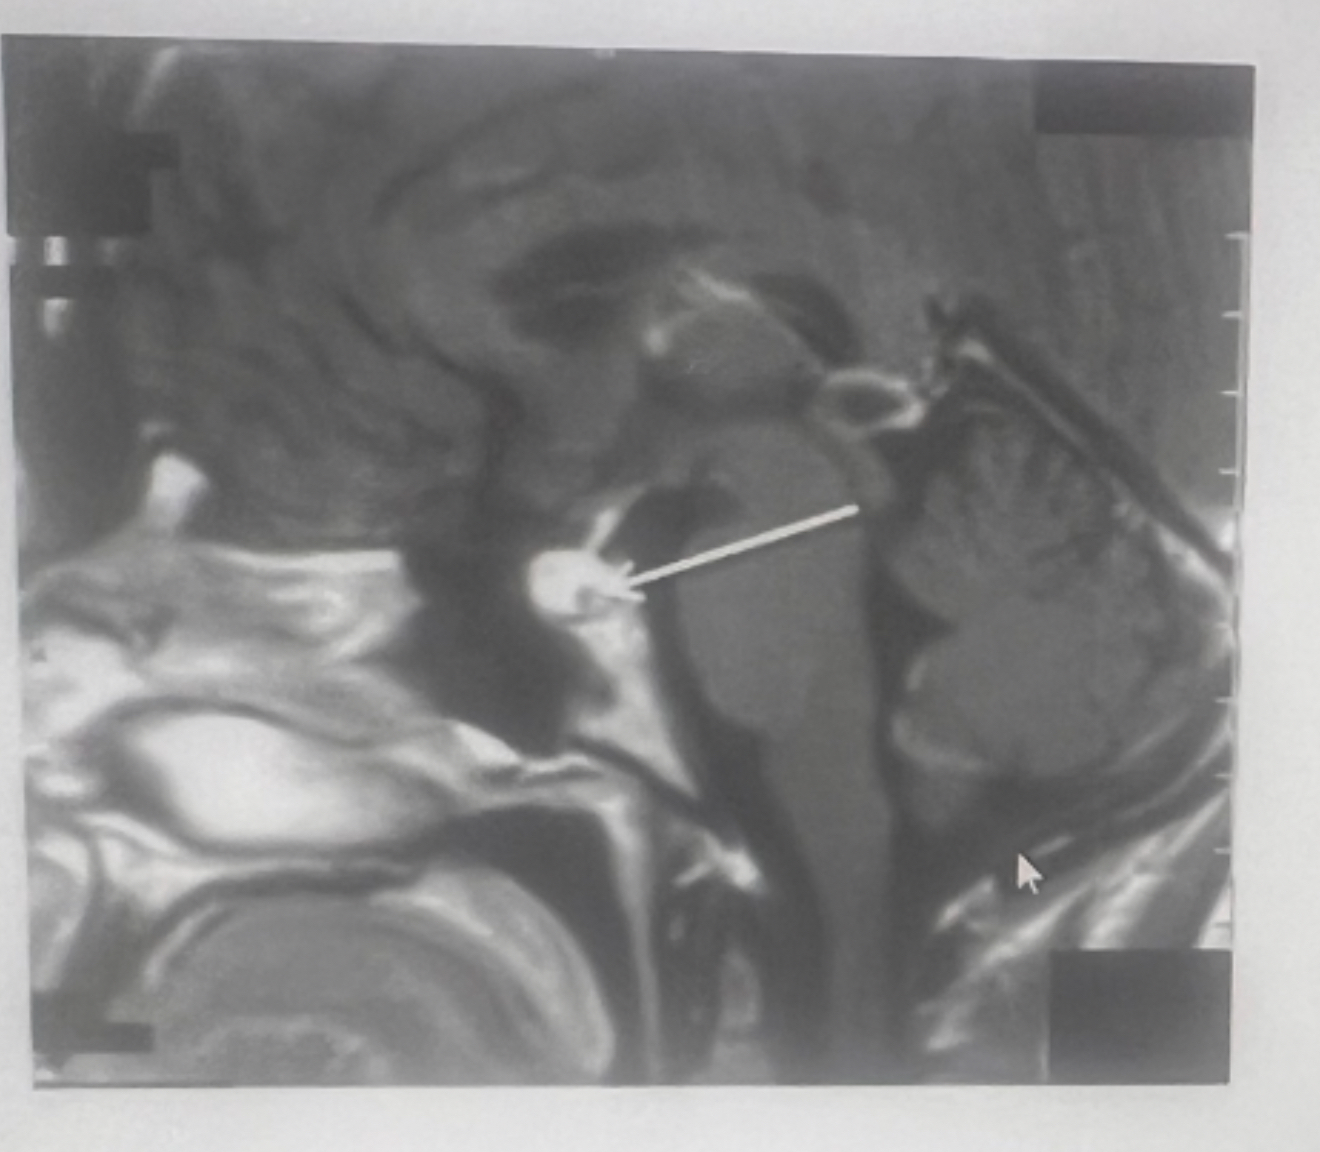

Q

What plane

A

Sagittal oblique TMJ (closed vs. open mouth)